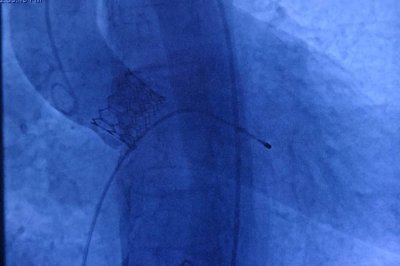

Aort kapak darlığının yaşla birlikte arttığını belirten Kardiyoloji Uzmanı Prof. Dr. Hasan Pekdemir, ameliyatsız gerçekleştirilen TAVI (Transkateter Aort Kapak İmplantasyonu) yöntemiyle hastalara büyük bir konfor sunduklarını ifade etti.